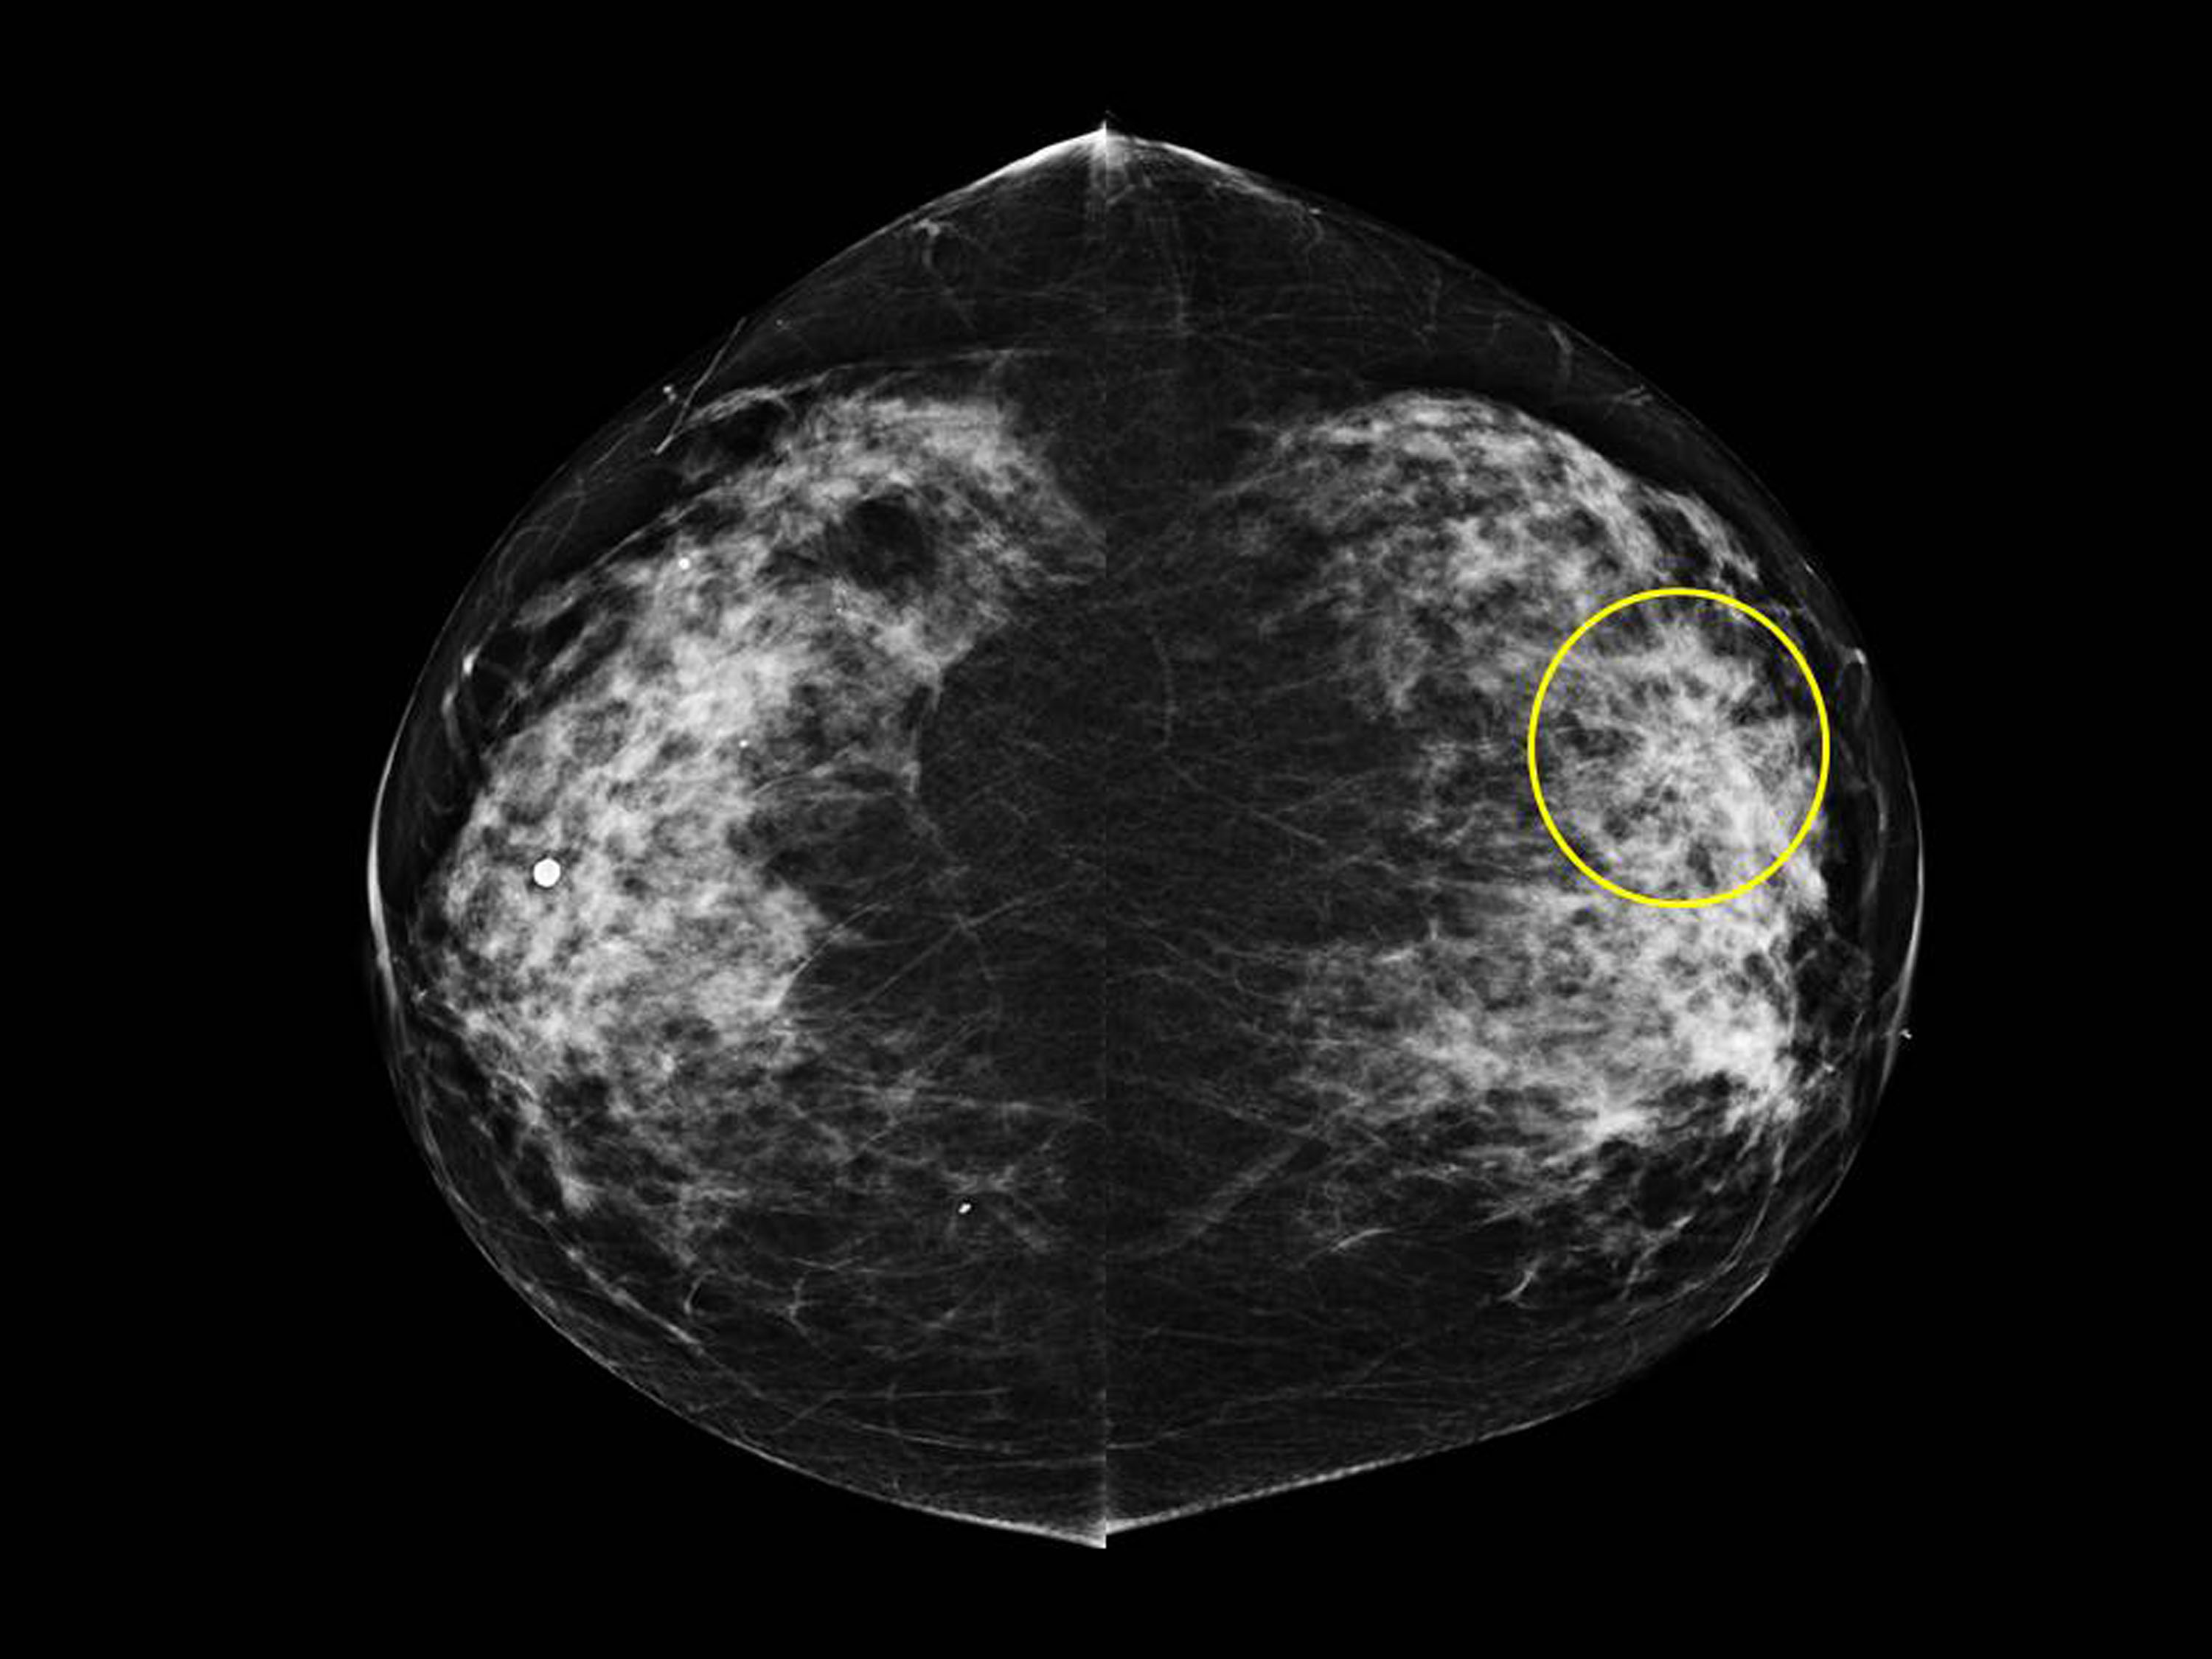

aibreastcancerdetectiononmammography RSNA Rsna Breast Imaging Mri of the breast has the highest sensitivity for breast cancer detection among current clinical imaging modalities and is. Screening, ai, ultrafast and parametric mri techniques are trending in this category. To avoid misclassifying a small superficial breast cancer as a benign dermal lesion, it is necessary to understand superficial breast and skin. Screening and ai continue to be key. Rsna Breast Imaging.